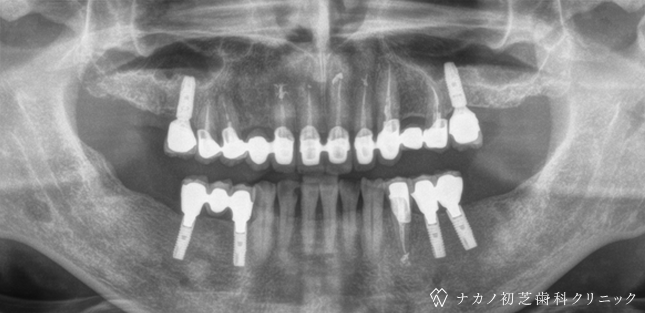

インプラント・13本 (60代女性)

BEFORE

AFTER

年齢 60代女性

治療内容 インプラント治療13本(骨造成の併用)

インプラント治療とは、歯を抜いた所にチタン製の人工歯根を埋入し、その上に歯を入れる方法です。骨を増やすことで、より審美的に治療が出来ました。費用 1本 400,000円(税込 440,000円)

リスク・副作用

腫れ・疼痛・違和感を感じるなどの症状を生じることがあります。